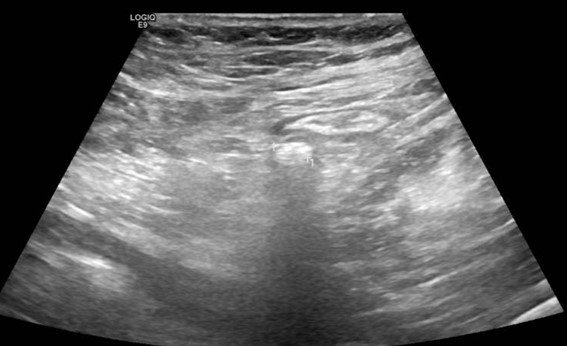

Ante la sospecha de cólico nefrítico complicado, se realiza ecografía abdominal, que muestra en fosa ilíaca izquierda, un foco ecogénico con sombra acústica posterior y engrosamiento de la pared intestinal de 6 mm. Se confirma mediante tomografía computarizada la presencia de divertículos en el colon izquierdo, con un divertículo engrosado entre el colon descendente y sigma, y discretos cambios inflamatorios pericólicos. Con mínimo líquido en la gotiera adyacente, sin colecciones ni burbujas de gas extraluminal.

Este caso subraya la importancia de una anamnesis completa y exploración física, que aunque no definitivas, ayudan a orientar el diagnóstico diferencial. Aunque diagnósticos comunes como el cólico nefrítico son frecuentes, es crucial no descartar otras patologías que podrían complicarse sin tratamiento adecuado. La ecografía, como herramienta inicial, permitió detectar signos de diverticulitis aguda no complicada, orientando el diagnóstico y tratamiento. Complementada por la tomografía computarizada, la ecografía demostró ser útil en el dolor abdominal localizado, destacando la importancia de un diagnóstico integral y el uso adecuado de herramientas disponibles.